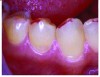

Figures 2 and 3. Abfraction lesions present on teeth with heavy indicator

markings. The marks indicate large contact areas present on the

cusp inclinations rather than the ideal small contact points on the cusp

tips. Reprinted with permission from Dr. Robert Palmer, DDS.

Figure 2

Figure 3

Occlusal loads, particularly lateral forces, may cause the teeth to flex. This flexure may in turn break the bonds in the hydroxyapatite, which leads to cracks and fractures in the enamel and underlying structures. Oblique stresses applied to the cuspal inclines, rather than cusp tips, put more stress on the tooth structure (Figure 2).3 Teeth are better able to withstand direct vertical pressure than lateral or oblique pressures. Heavy occlusal contact areas, determined by heavy markings using pressure-detecting sheets, have been significantly linked to the occurrence of cervical lesions (Figure 3).2